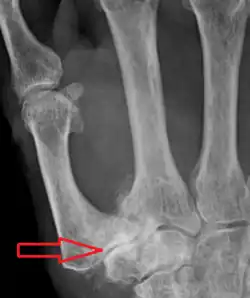

| Osteoarthritis of the trapeziometacarpal joint | |

Trapeziometacarpal osteoarthritis (TMC OA) is, also known as osteoarthritis at the base of the thumb, thumb carpometacarpal osteoarthritis, basilar (or basal) joint arthritis, or as rhizarthrosis.[3][1][2] This joint is formed by the trapezium bone of the wrist and the metacarpal bone of the thumb. This is one of the joints where most humans develop osteoarthritis with age.[4] Osteoarthritis is age-related loss of the smooth surface of the bone where it moves against another bone (cartilage of the joint).[3][5] In reaction to the loss of cartilage, the bones thicken at the joint surface, resulting in subchondral sclerosis. Also, bony outgrowths, called osteophytes (also known as "bone spurs"), are formed at the joint margins.[6]